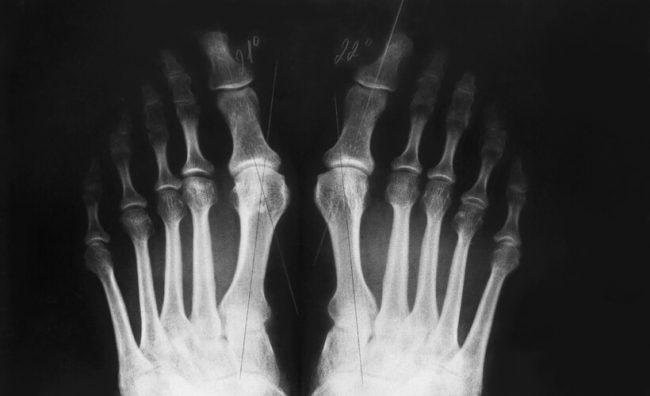

La patología reumatológica es tratada por especialistas traumatólogos, que se encargan de prevenir, diagnosticar y tratar las enfermedades musculoesqueléticas y autoinmunes sistémicas. Y hay más de 200 enfermedades reumáticas que pueden afectar a cualquier edad. Estas enfermedades afectan a uno de cada cuatro adultos en España, convirtiéndola en la segunda causa de consulta, tras las…